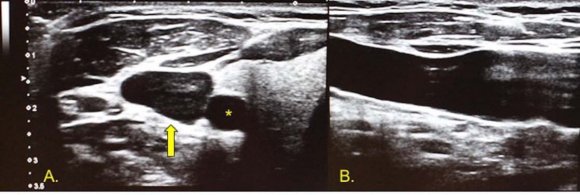

Conducting the Process Knowledge of the technical aspects of ultrasound and the characteristics of the equipment optimizes assessment prior to conducting the procedure as well as its correct display (26). High-frequency Bmode ultrasound serves to evaluate structures displayed on a gray-scale image, in real time and in different anatomical planes. Venous vessels are visualized as anechoic structures with echogenic thin and regular walls, most of the time exhibiting a greater diameter than their accompanying arteries. In some locations, with excellent image quality, it is possible to identify the venous valves which should be avoided when inserting catheters (27,28). Depending on transducer orientation, the venous vessels and the catheter are identified as tubular structures (in a longitudinal plane of the transducer with the vessel) or oval structures (if the transducer is placed transverse or axial to the axis of the vessel) (Image 1) (6). However, in some special cases, such as the catheterization of the internal jugular vein, it is possible to perform oblique orientations, where the vessel is projected in the axial plane and the needle in the longitudinal plane (scheme 1) (29). Under normal conditions the venous vessels collapse with gentle compression with the transducer and, increase their caliber with the Valsalva maneuvers (Image 2). Knowledge of normal vascular anatomy, anatomical variants and possible pathological conditions that may hinder the correct characterization of venous vessels is essential (30,31). In most cases, the internal jugular vein is located anterolateral to the common carotid artery (image 3) presenting a diameter that varies between 5 and 11.5 mm. The right vein diameter is relatively greater than the left, in up to 65% of cases (32), and the right is also generally preferred as the first option for catheter placement.

Image 2: transverse image of the internal jugular vein at rest (A), during the Valsalva maneuver (B), there is an increase in caliber. The common femoral vein is made up of its tributaries: the deep femoral vein and the femoral vein (previously known as the superficial femoral vein), is located approximately 9 cm from the inguinal ligament and medial to the common femoral artery (Image 4). Proximally, the femoral vein runs medially to the artery, but, distally, it crosses over it and is located laterally (33). In some percentages and especially in the pediatric population, the femoral artery may adopt an anterior location to the vein (34).